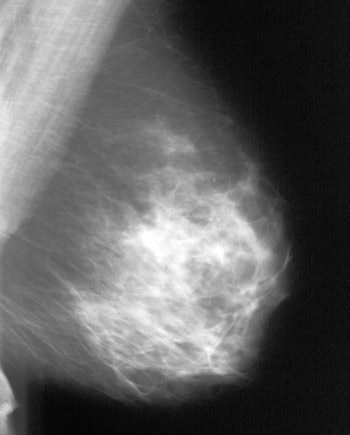

![]() |

| An example of a less-dense glandular pattern more often seen as women reach middle age. Breast cancer is easier to detect against a background of more fatty tissue. Image courtesy of Dr. Michael Linver. |